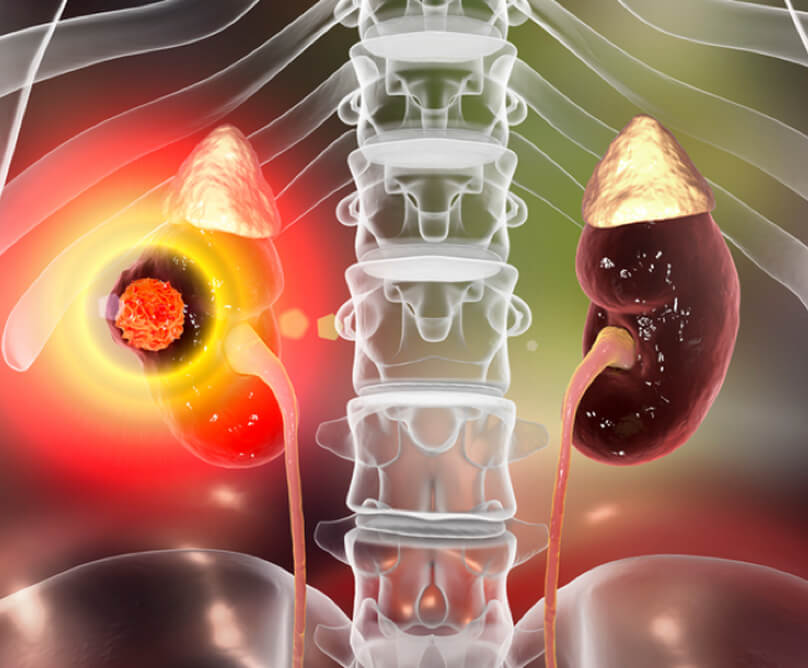

Το κύριο όργανο του ουροποιητικού συστήματος είναι οι νεφροί, ένας αριστερός κι ένας δεξιός. Έχουν σχήμα φασολιού και βρίσκονται στα πλάγια της σπονδυλικής στήλης κάτω από το διάφραγμα.

Οι νεφροί είναι ισχυρά χημικά εργοστάσια με ποικίλες λειτουργίες. Φιλτράρουν το αίμα και το απαλλάσσουν από τοξίνες και ουσίες μέσω των ούρων. Ρυθμίζουν την ισορροπία των υγρών, του άλατος και των ηλεκτρολυτών, παράγουν ορμόνες που καθορίζουν την αρτηριακή πίεση, την παραγωγή ερυθρών αιμοσφαιρίων του αίματος και το μεταβολισμό του ασβεστίου των οστών.

- Ο καρκίνος του νεφρού είναι η τρίτη συχνότερη κακοήθεια του ουροποιητικού συστήματος και παρατηρείται μια σταθερή αύξηση της επίπτωσής του παγκοσμίως τις τελευταίες 2 δεκαετίες.

- Σήμερα, η διάγνωση σε ποσοστό μεγαλύτερο του 50% γίνεται σε τυχαίο απεικονιστικό έλεγχο (αξονική τομογραφία, υπερηχογράφημα), μιας και η νόσος δεν παρουσιάζει πρώιμα συμπτώματα.